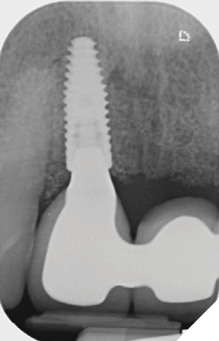

Radiographic examination shows the upper left lateral incisor tooth has decayed through and through and the upper right central incisor tooth is heavily root treated and filled (Figs. 1-2).

Fig. 1

Fig. 2